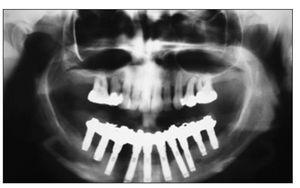

Figura 1 Radiografías periapicales realizadas en 1989 a una mujer de 31 años que muestran una amplia pérdida de hueso vertical como consecuencia de una enfermedad periodontal avanzada.

Figura 2 Ortopantomograma realizado en 1994 que muestra el tratamiento de la paciente con una PDF implantosoportada en el maxilar inferior y la retención de los dientes en el maxilar superior.